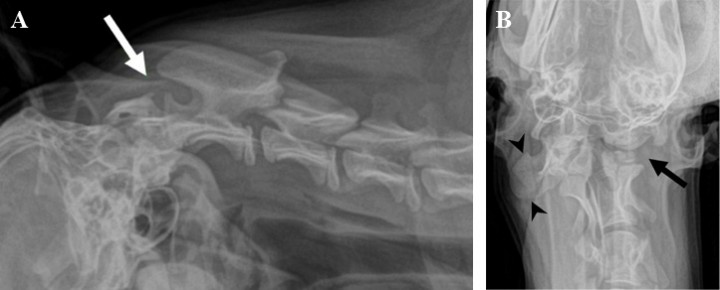

Es referida para evaluación neurológica una perra mestiza de 4 meses de edad y 23 kilos de peso por presentar dolor cervical y tetraparesia de 4 días de evolución tras sufrir un traumatismo. En la exploración física se palpó una asimetría del atlas, que parecía rotado, lo que hacía que el paciente sufriese una desviación severa del cuello con gran dolor a la manipulación. El examen neurológico reveló tetraparesia ambulatoria severa con retraso simétrico de las reacciones posturales en las cuatro extremidades. Los reflejos medulares y la evaluación de los pares craneales eran normales. Este examen fue compatible con una afección focal o difusa de los segmentos medulares C1 - C5. El diagnóstico diferencial, teniendo en cuenta la historia clínica y la exploración física, incluyó principalmente procesos de carácter malformativo, sin poder descartarse enfermedades traumáticas, inflamatorias o neoplásicas. Se realizaron radiografías de la columna cervical en proyección lateral y ventrodorsal donde se apreció una inestabilidad de la articulación AA evidenciada por aumento de distancia entre la lámina del atlas y la apófisis espinosa del axis (Fig. 1A). Sin embargo, el hallazgo más relevante consistió en la ausencia del ala (apófisis transversa modificada) y la mitad izquierda del cuerpo del atlas (Fig. 1B). Posteriormente se procedió a la realización de una tomografía computarizada (TC) donde se confirmó la existencia de una malformación cervical con desplazamiento rostral del axis, que hacía que el diente del axis sobrepasase el límite craneal del cuerpo del atlas y los cóndilos del occipital, quedando en contacto con el aspecto ventral de la médula oblonga (signo radiológico denominado “invaginación basilar” en medicina humana) (Fig. 2, A y B). El atlas presentaba una agenesia de su mitad izquierda y en su lugar se apreciaron dos pequeños núcleos óseos independientes que ocupaban una posición dorsolateral izquierda no unidos con el resto de estructuras óseas (Fig. 2, C). Aunque el arco derecho del atlas quedaba íntimamente asociado con el cóndilo derecho del occipital, se evidenció una conformación atlanto-occipital derecha normal, con una línea articular bien formada pero rotada (Fig. 2, B). En el aspecto ventral del atlas se observaba el “intercentrum” 1, así como la sincondrosis neurocentral derecha (Fig. 2, B). Sin embargo, la sincondrosis neurocentral izquierda y la dorsal no podían ser evidenciadas debido a la ausencia del centro de osificación del arco neural izquierdo (Fig. 2, C). Todas estas alteraciones hacían que la articulación atlanto-occipital quedase rotada, haciendo que la cabeza girase en contra del sentido de las agujas del reloj visto desde un plano dorsal (Fig. 3, A y B). El agujero vertebral lateral y el agujero transverso del arco derecho del atlas estaban correctamente formados (Fig. 3, A). Por otro lado, se apreció como el aspecto craneal del cuerpo del axis y la apófisis odontoides estaban deformados, engrosados e hiperostóticos (Fig. 2, A). El borde craneal de la apófisis espinosa del axis quedaba deformado con desviación derecha, haciendo leve prominencia sobre el atlas (Figs. 2A y 3A). Posteriormente, se decidió realizar una resonancia magnética de la columna cervical para valorar el parénquima medular, donde se evidenció una severa compresión dorsoventral de la médula espinal a nivel de la articulación AA con obliteración del espacio subaracnoideo ventral y dorsal (Fig. 4). Las secuencias ponderadas en T2 demostraron la hiperintensidad del parénquima medular en el punto de mayor compromiso (Fig. 4).

<p><strong>(A) </strong>Radiografía lateral de la columna cervical. Nótese el desplazamiento dorsal del cuerpo del axis con respecto al atlas y la distancia anormalmente amplia entre la apófisis espinosa del axis y el arco del atlas (flecha).<strong> (B) </strong>Radiografía ventrodorsal de la columna cervical craneal. Nótese la ausencia de la mitad izquierda del atlas (flecha). Compárese con el lado contrario en el que se puede evidenciar el ala del atlas formado normalmente (puntas de flecha) quedando asociado a una rotación anómala de la cabeza.</p>

Figura 1

(A) Radiografía lateral de la columna cervical. Nótese el desplazamiento dorsal del cuerpo del axis con respecto al atlas y la distancia anormalmente amplia entre la apófisis espinosa del axis y el arco del atlas (flecha). (B) Radiografía ventrodorsal de la columna cervical craneal. Nótese la ausencia de la mitad izquierda del atlas (flecha). Compárese con el lado contrario en el que se puede evidenciar el ala del atlas formado normalmente (puntas de flecha) quedando asociado a una rotación anómala de la cabeza.